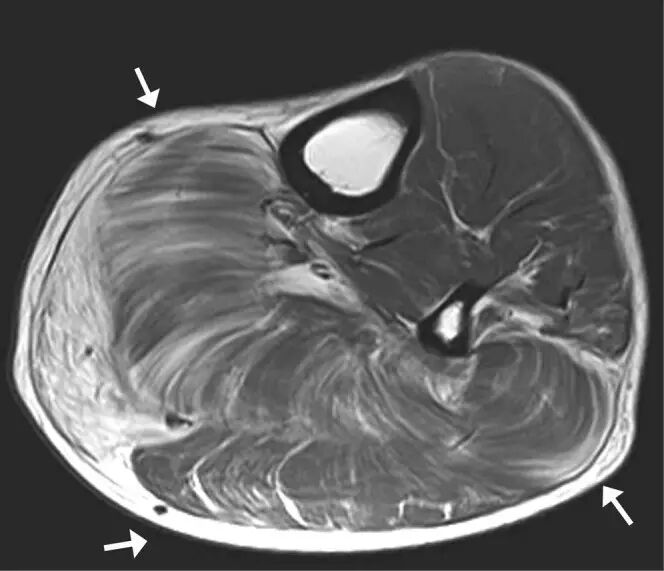

![]()

图24.骨骼肌损伤和肌坏死。 该患者,在坠落后发生的右大腿中的受污染伤口导致感染性肌坏死。 (a)轴向T2加权MRI图像显示肿大的内收肌和股二头肌----(肌肉)由于水肿扩散高信号强度。 在大收肌(箭头)中看到中心区域与流体聚集相一致。 (b)冠状动脉脂肪抑制T2加权磁共振成像显示弥漫性水肿在大腿近端的后房(箭头)。 其信号空隙肌内气体被看作指示严重感染(气性坏疽)的存在(箭头)。 感染区域的培养物显示破伤风杆菌。